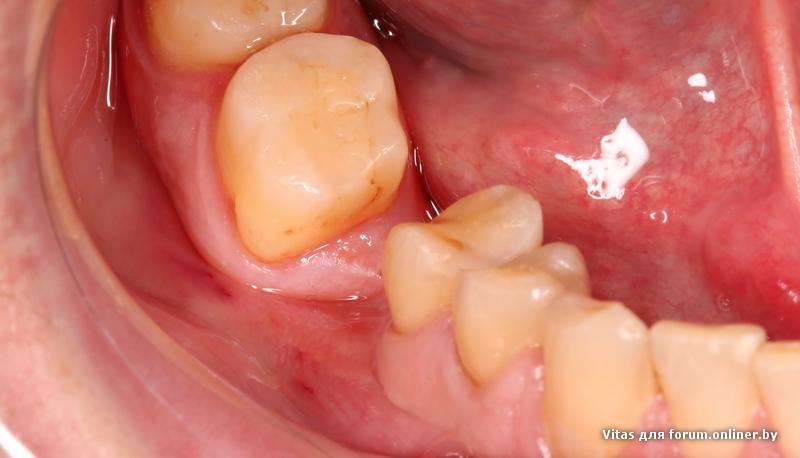

Для любителей кровавых фото.

На бруксизм не обращайте внимания.

чего эта фотка онлайнером переворачивается не понятно....